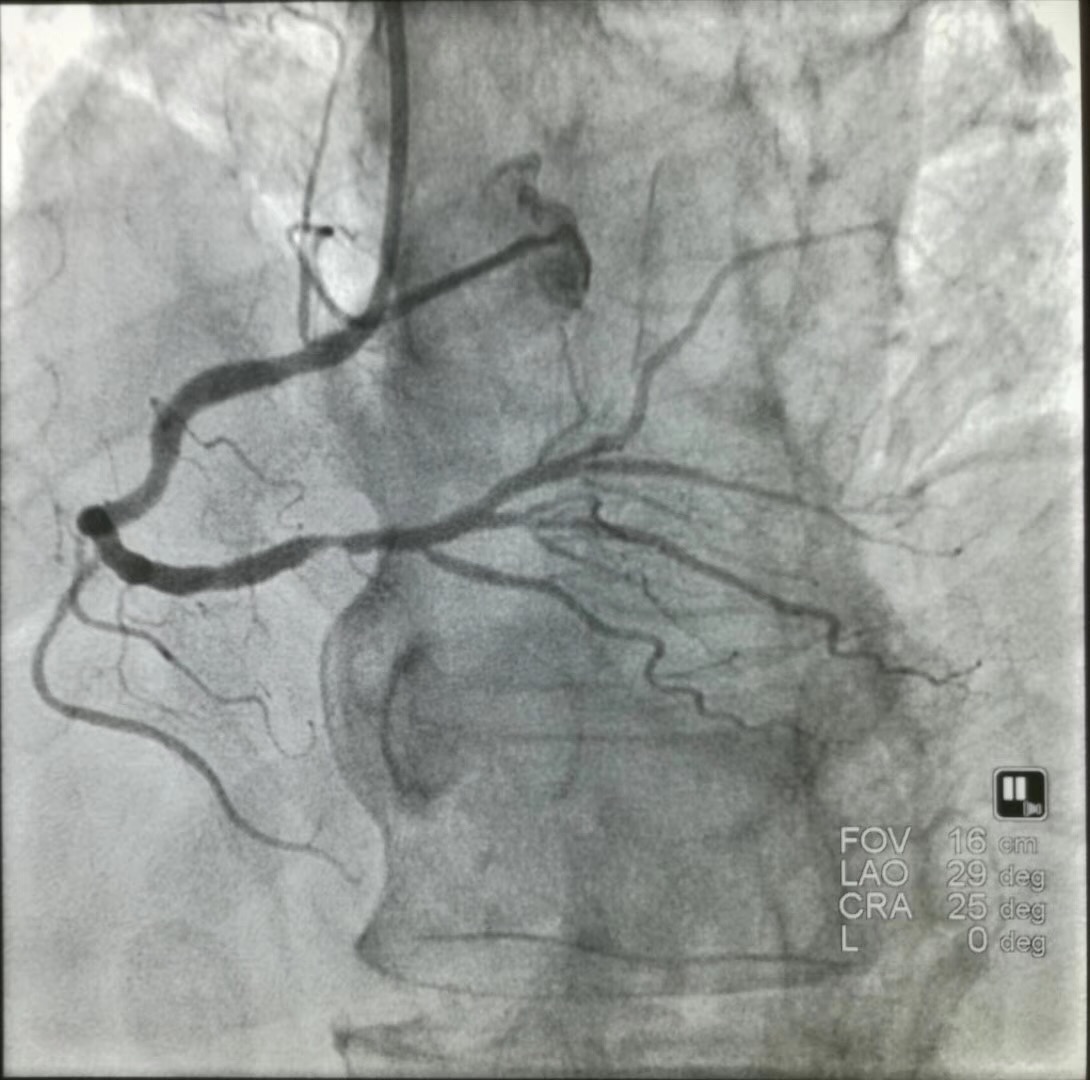

而冠脉支架更直接,是从手上的桡动脉或腿上的股动脉穿刺进去,通过导管把冠脉支架直接送到心脏狭窄部位,然后释放支架,起到立竿见影的效果,这种操作就是急诊PCI 。对于冠脉支架,血管开通率更高,年龄也不是问题,也不存在误诊的问题。但急诊PCI的缺点是技术要求高,不是所有医院都有条件做,只有当地一些三甲医院才能满足这样的人员配置。其次是发病后到三甲医院进行急诊PCI需要时间,可能会延误急性心梗的治疗,如果短时间内无条件到达三甲医院的胸痛中心导管室,不要再去三甲医院住院,应就近抢救。